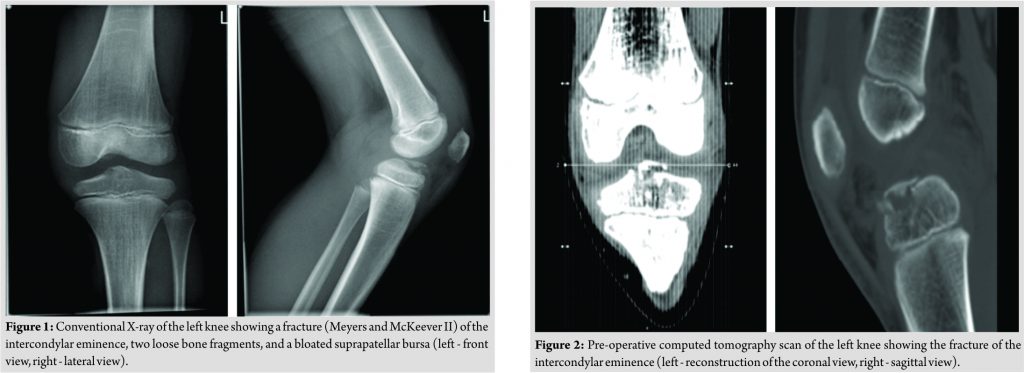

A male Caucasian 8-year-old child presented at the hospital’s emergency department in Belgium. The circumstances of the accident were reported as a fall on the left knee complicated by a contact trauma with another child. At consultation presenting, complaints were a sharp pain in his left knee and difficulties to walk. The pain was scored as 4/10 on the visual analogue scale. In clinical examination, anterior pressure pain, swelling, and a restricted range of motion(flexion up to 100° and extension deficit of 5°) were the main findings. Performing ananterior drawer test and Lachman test, no laxity was documented. On conventional anteroposterior and lateral view of the X-ray, a minimal displaced fracture of the intercondylar eminence, two loose bone fragments, and a bloated suprapatellar bursa indicating hemarthrosis could be evidenced (Fig. 1). A CT scan confirmed a fracture of the intercondylareminence (Fig. 2).

The fracture was classified as Meyers and McKeever Type II [4]. The initial treatment provided an adequate pain management with appropriate analgesics and plaster immobilization in 0–5° of flexion. Based on the clinical and radiological findings, a knee arthroscopy was performed 3daysafter injury. The indication for arthroscopic surgery was removal of the intra-articular bony fragments and to evaluate whether the fracture was stable. The fracture of the proximal tibia was visualized through arthroscopy (Fig. 3).